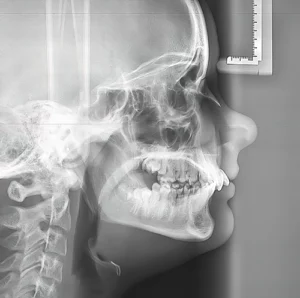

The first method dental implants assist forestall bone loss is by stimulating the jawbone. When a pure tooth is current, it exerts stress on the jawbone throughout actions like chewing. This stress stimulates the bone, preserving it sturdy and wholesome. When a tooth is misplaced, this stimulation can also be misplaced, resulting in bone resorption. Dental implants mimic the operate of pure tooth. They’re anchored into the jawbone and act like tooth roots. Chewing with an implant gives the required stimulation to the bone, stopping bone loss and even selling bone progress in some circumstances.

Dental implants supply a long-term resolution to tooth loss, not like different tooth alternative choices like dentures or dental bridges, which can must be changed or adjusted over time. As a result of implants are product of biocompatible supplies resembling titanium, they fuse with the jawbone in an osseointegration course of. This fusion gives a secure basis for the implant and ensures it features like a pure tooth root. This long-term stability is essential for sustaining bone well being over time. By integrating with the bone, dental implants forestall the bone resorption that sometimes follows tooth loss, providing a sturdy and lasting resolution for sustaining each operate and aesthetics.